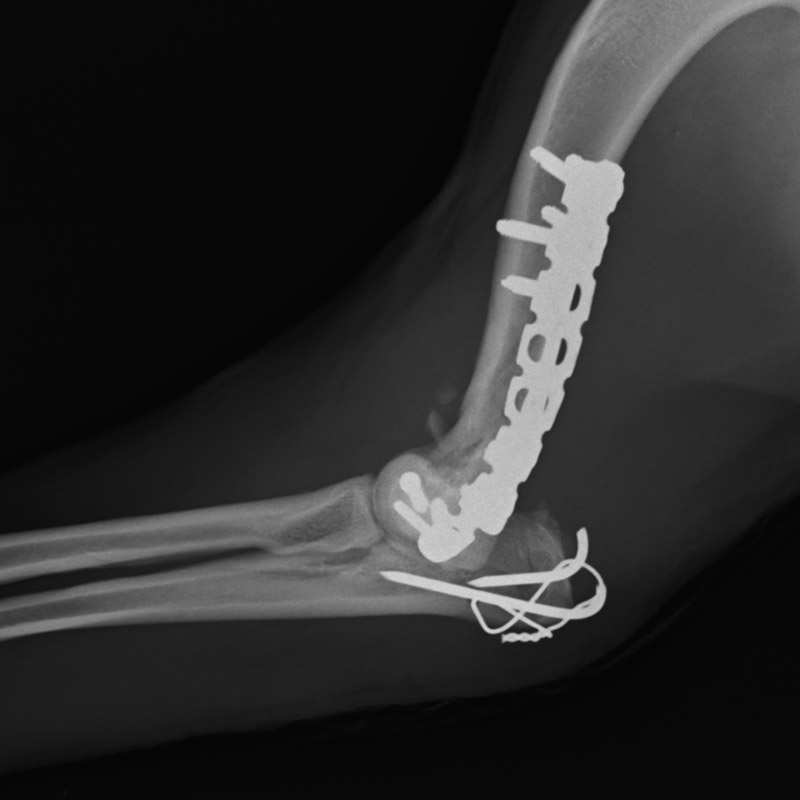

肘関節内骨折

アメリカン・コッカー・スパニエル(5歳)

車の窓から落下

手術前

手術後